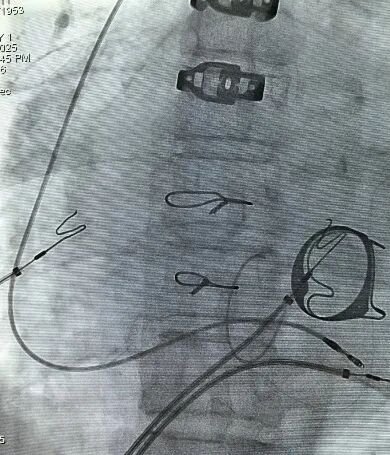

考虑患者有风湿性心脏病换瓣术、心功能不全和房颤伴慢心室率,术后起搏比例超过40%,单纯右室心尖或间隔起搏可能引起或加重心功能不全;经术前手术组讨论并经患者及家属知情同意决定于2025-09-15行左束支起搏植入术。手术成功行左侧腋静脉穿刺成功后,标准方法置入预制间隔弯鞘(K鞘)和电极;因为右房巨大支撑鞘无法到位,电极无法得到鞘的支撑,电极无法旋入左束支区域,术中操作近一小时,常规标准方法行左束支区域电极植入失败(图1),如果行右侧间隔植入,这样患者无法从这一先进起搏技术中获益;单其俊教授建议根据这个患者心脏特殊情况,用加硬(红色)导丝手塑3D间隔异型弯(根据患者心脏大小个体化量身定制)直接用ABBOTT普通心室螺旋电极进行左束支植入,通过20分钟艰难努力手术终于成功(图2),所有起搏参数满意(图3-5)。

图2 手塑导丝3D间隔异型弯(量身定制)直接用普通心室螺旋电极旋入左束支区域,手术成功X线影像图,左图后前位,中图右前斜位(RAO30),右图左前斜位(LAO40);可见置换的二尖瓣和成型的三尖瓣瓣环。